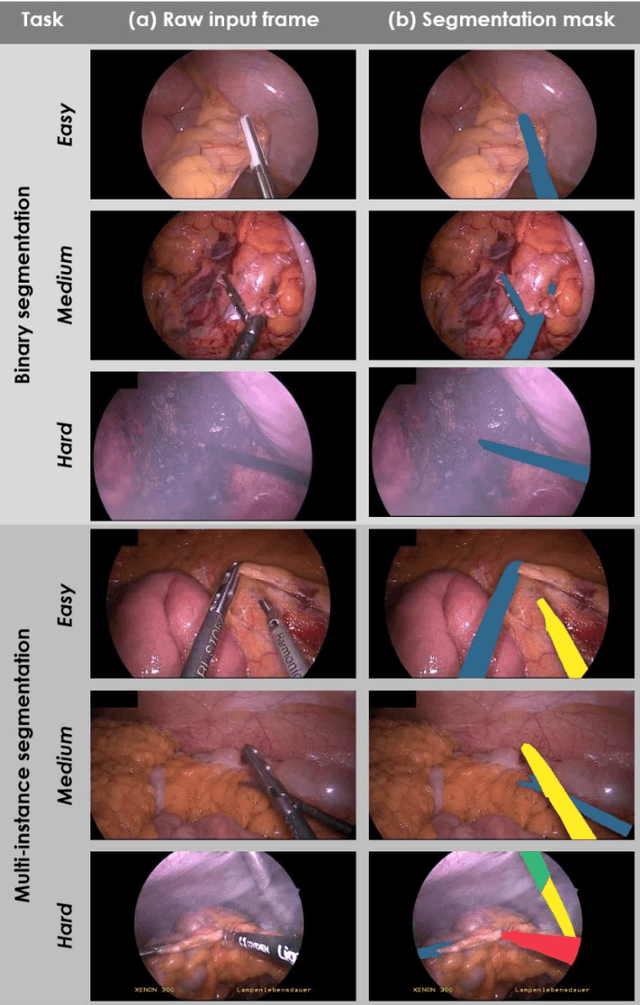

Abstract:Intraoperative tracking of laparoscopic instruments is often a prerequisite for computer and robotic-assisted interventions. While numerous methods for detecting, segmenting and tracking of medical instruments based on endoscopic video images have been proposed in the literature, key limitations remain to be addressed: Firstly, robustness, that is, the reliable performance of state-of-the-art methods when run on challenging images (e.g. in the presence of blood, smoke or motion artifacts). Secondly, generalization; algorithms trained for a specific intervention in a specific hospital should generalize to other interventions or institutions. In an effort to promote solutions for these limitations, we organized the Robust Medical Instrument Segmentation (ROBUST-MIS) challenge as an international benchmarking competition with a specific focus on the robustness and generalization capabilities of algorithms. For the first time in the field of endoscopic image processing, our challenge included a task on binary segmentation and also addressed multi-instance detection and segmentation. The challenge was based on a surgical data set comprising 10,040 annotated images acquired from a total of 30 surgical procedures from three different types of surgery. The validation of the competing methods for the three tasks (binary segmentation, multi-instance detection and multi-instance segmentation) was performed in three different stages with an increasing domain gap between the training and the test data. The results confirm the initial hypothesis, namely that algorithm performance degrades with an increasing domain gap. While the average detection and segmentation quality of the best-performing algorithms is high, future research should concentrate on detection and segmentation of small, crossing, moving and transparent instrument(s) (parts).